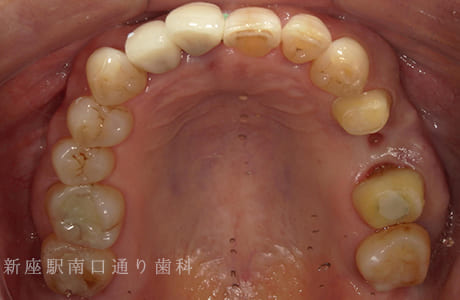

CASE.04

右上にフルジルコニアブリッジで

修復した症例

術前

術中

術後年

- 主訴

- 歯がないところを治したい

- 治療法

- 右上にフルジルコニアブリッジで修復

- 治療期間

- 1ヶ月半

- 費用

- ¥280,000(税込)

【リスク・副作用】

過度の咬合や衝撃で割れることがあります。治療直後は歯や歯茎に一時的な違和感や痛みが出ることがあります。